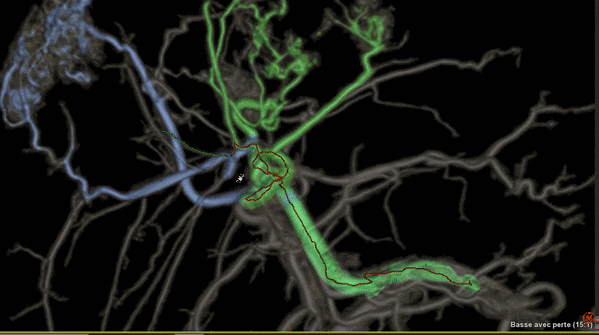

Liver ASSIST V.I,一種增強(qiáng)型軟件

可利用分析工具幫助臨床醫(yī)生克服腫瘤治療的挑戰(zhàn),例如,阻斷肝部腫瘤周邊供養(yǎng)血管是一種有效的介入治療方法,Liver ASSIST V.I可以通過精確高效的血管解剖分析來界定并精準(zhǔn)選擇注射點(diǎn),如同Google地圖一樣進(jìn)行路徑引導(dǎo),可以術(shù)前進(jìn)行手術(shù)預(yù)演來提供手術(shù)的精準(zhǔn)度,減少手術(shù)并發(fā)癥,讓人工智能的智慧在介入治療中閃光。